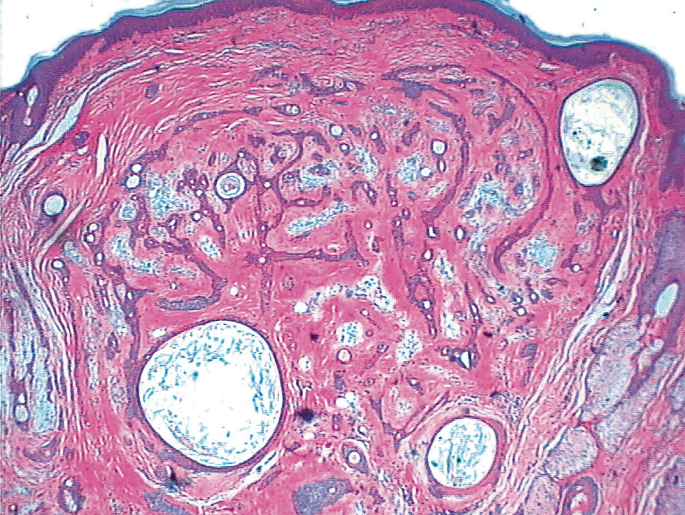

Pathology Outlines Anatomy Histology

Anatomy And Histology Of The Pancreas Pancreapedia

Tumors Of The Skin Springerlink

Pancreas Histology